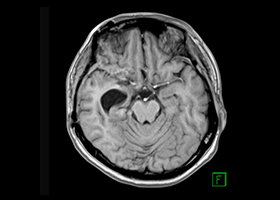

症例3)31歳男性、延髄前面巨大舌下神経鞘腫

[画像所見]

-

嚥下困難、四肢麻痺で発症しました。 -

術前 -

術後 -

術後、患者さんは元気に自宅退院されました。